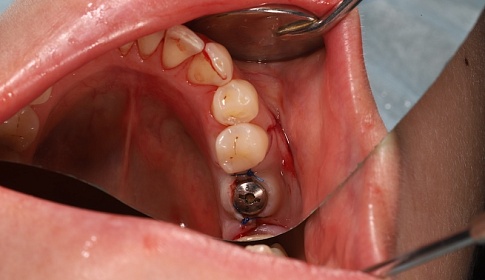

1 этап-хирургический:

- рассечение десны (готовится ложа для имплантата);

- устанавливается имплантат;

- ушиваются десневые ткани для изоляции имплантата.

Через 3 месяца после после полного приживления имплантата ткани десны повторно рассекают и устанавливают формирователь десны (готовится место для коронки).

2 этап-ортодонтический: через 3 недели после установки формирователя десны начинается протезирование.